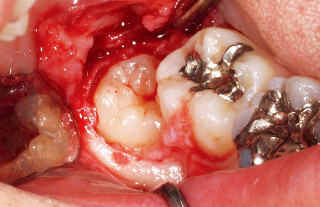

図5 ボリュームレンダリング画像で設定した切開部から粘膜剥離を行うと画像とほぼ同じ状態が現れる。これにより切開量の過不足が起こらず、適正な術野を確保することができる。

図11 切れ込みを入れた歯頸部にエレベーターを入れ、頰側歯槽骨を支点にして上方に持ち上げるようにして脱臼させた。容易に脱臼し、スムーズに抜歯が行えた。